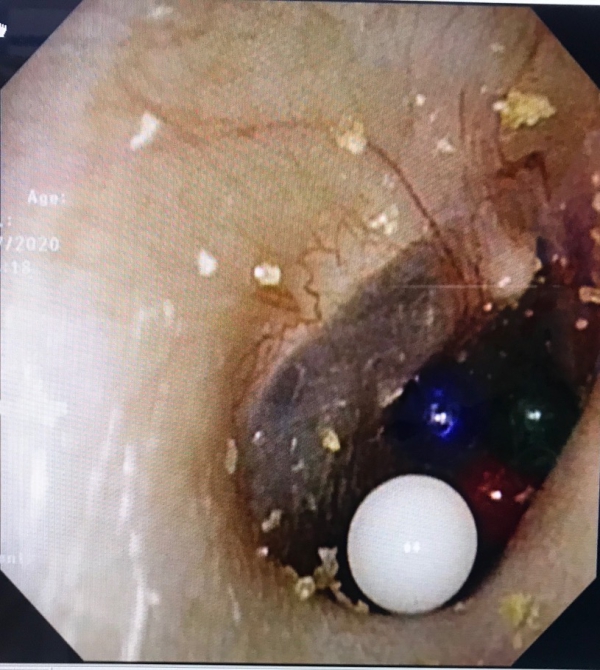

7月3日临近下班,淘淘捂着疼痛的右耳来到长春市儿童医院眼耳鼻喉科。经电子耳内窥镜检查,医生发现他的右耳内有4颗彩色小圆粒,位置都贴近鼓膜,而且填满了耳道。

长春市儿童医院眼耳鼻喉科副主任李莉萍利用耵聍钩开始取。因为贴近鼓膜,取时须轻些再轻些。而弹珠呈小颗粒状,特别硬,耵聍钩不好往出钩。2分钟后,离鼓膜最远的白色弹珠取出来了。取其他3颗就比较困难了,珠子之间相互挤压,与耳道壁及鼓膜紧密接触,只能用耵聍钩从珠子前方、下方寻找缝隙,从里往外将弹珠带出。经过努力,后3颗弹珠也陆续取出。

4颗取完后,医生用耳内镜再次检查,隐约发现在鼓膜凹陷的位置有一个红色的东西,紧紧地卡在缝隙里。经仔细辨认,确认是又一个吸水弹珠!红色的弹珠与充血的鼓膜非常相似,如果不是细心,还真发现不了它。

因为红色弹珠位置太深,离鼓膜最近,取它格外费劲。10多分钟后,才把它弄出来。